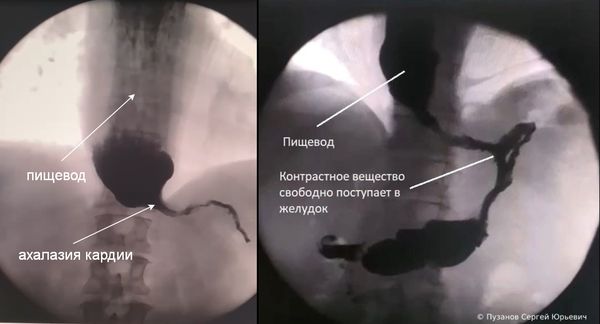

- Рентгенографию с контрастом — в качестве контраста используют бариевую взвесь. В ходе процедуры врач может увидеть расширение и S-образное искривление пищевода, газовый пузырь и момент открытия нижнего пищеводного сфинктера, он также оценивает скорость продвижения контрастной массы [1] .

- Эзофагогастродуоденоскопию (ЭГДС) — помогает исключить псевдоахалазии. С помощью этой процедуры можно точно определить степень расширения пищевода и увидеть, есть ли в нём пища.